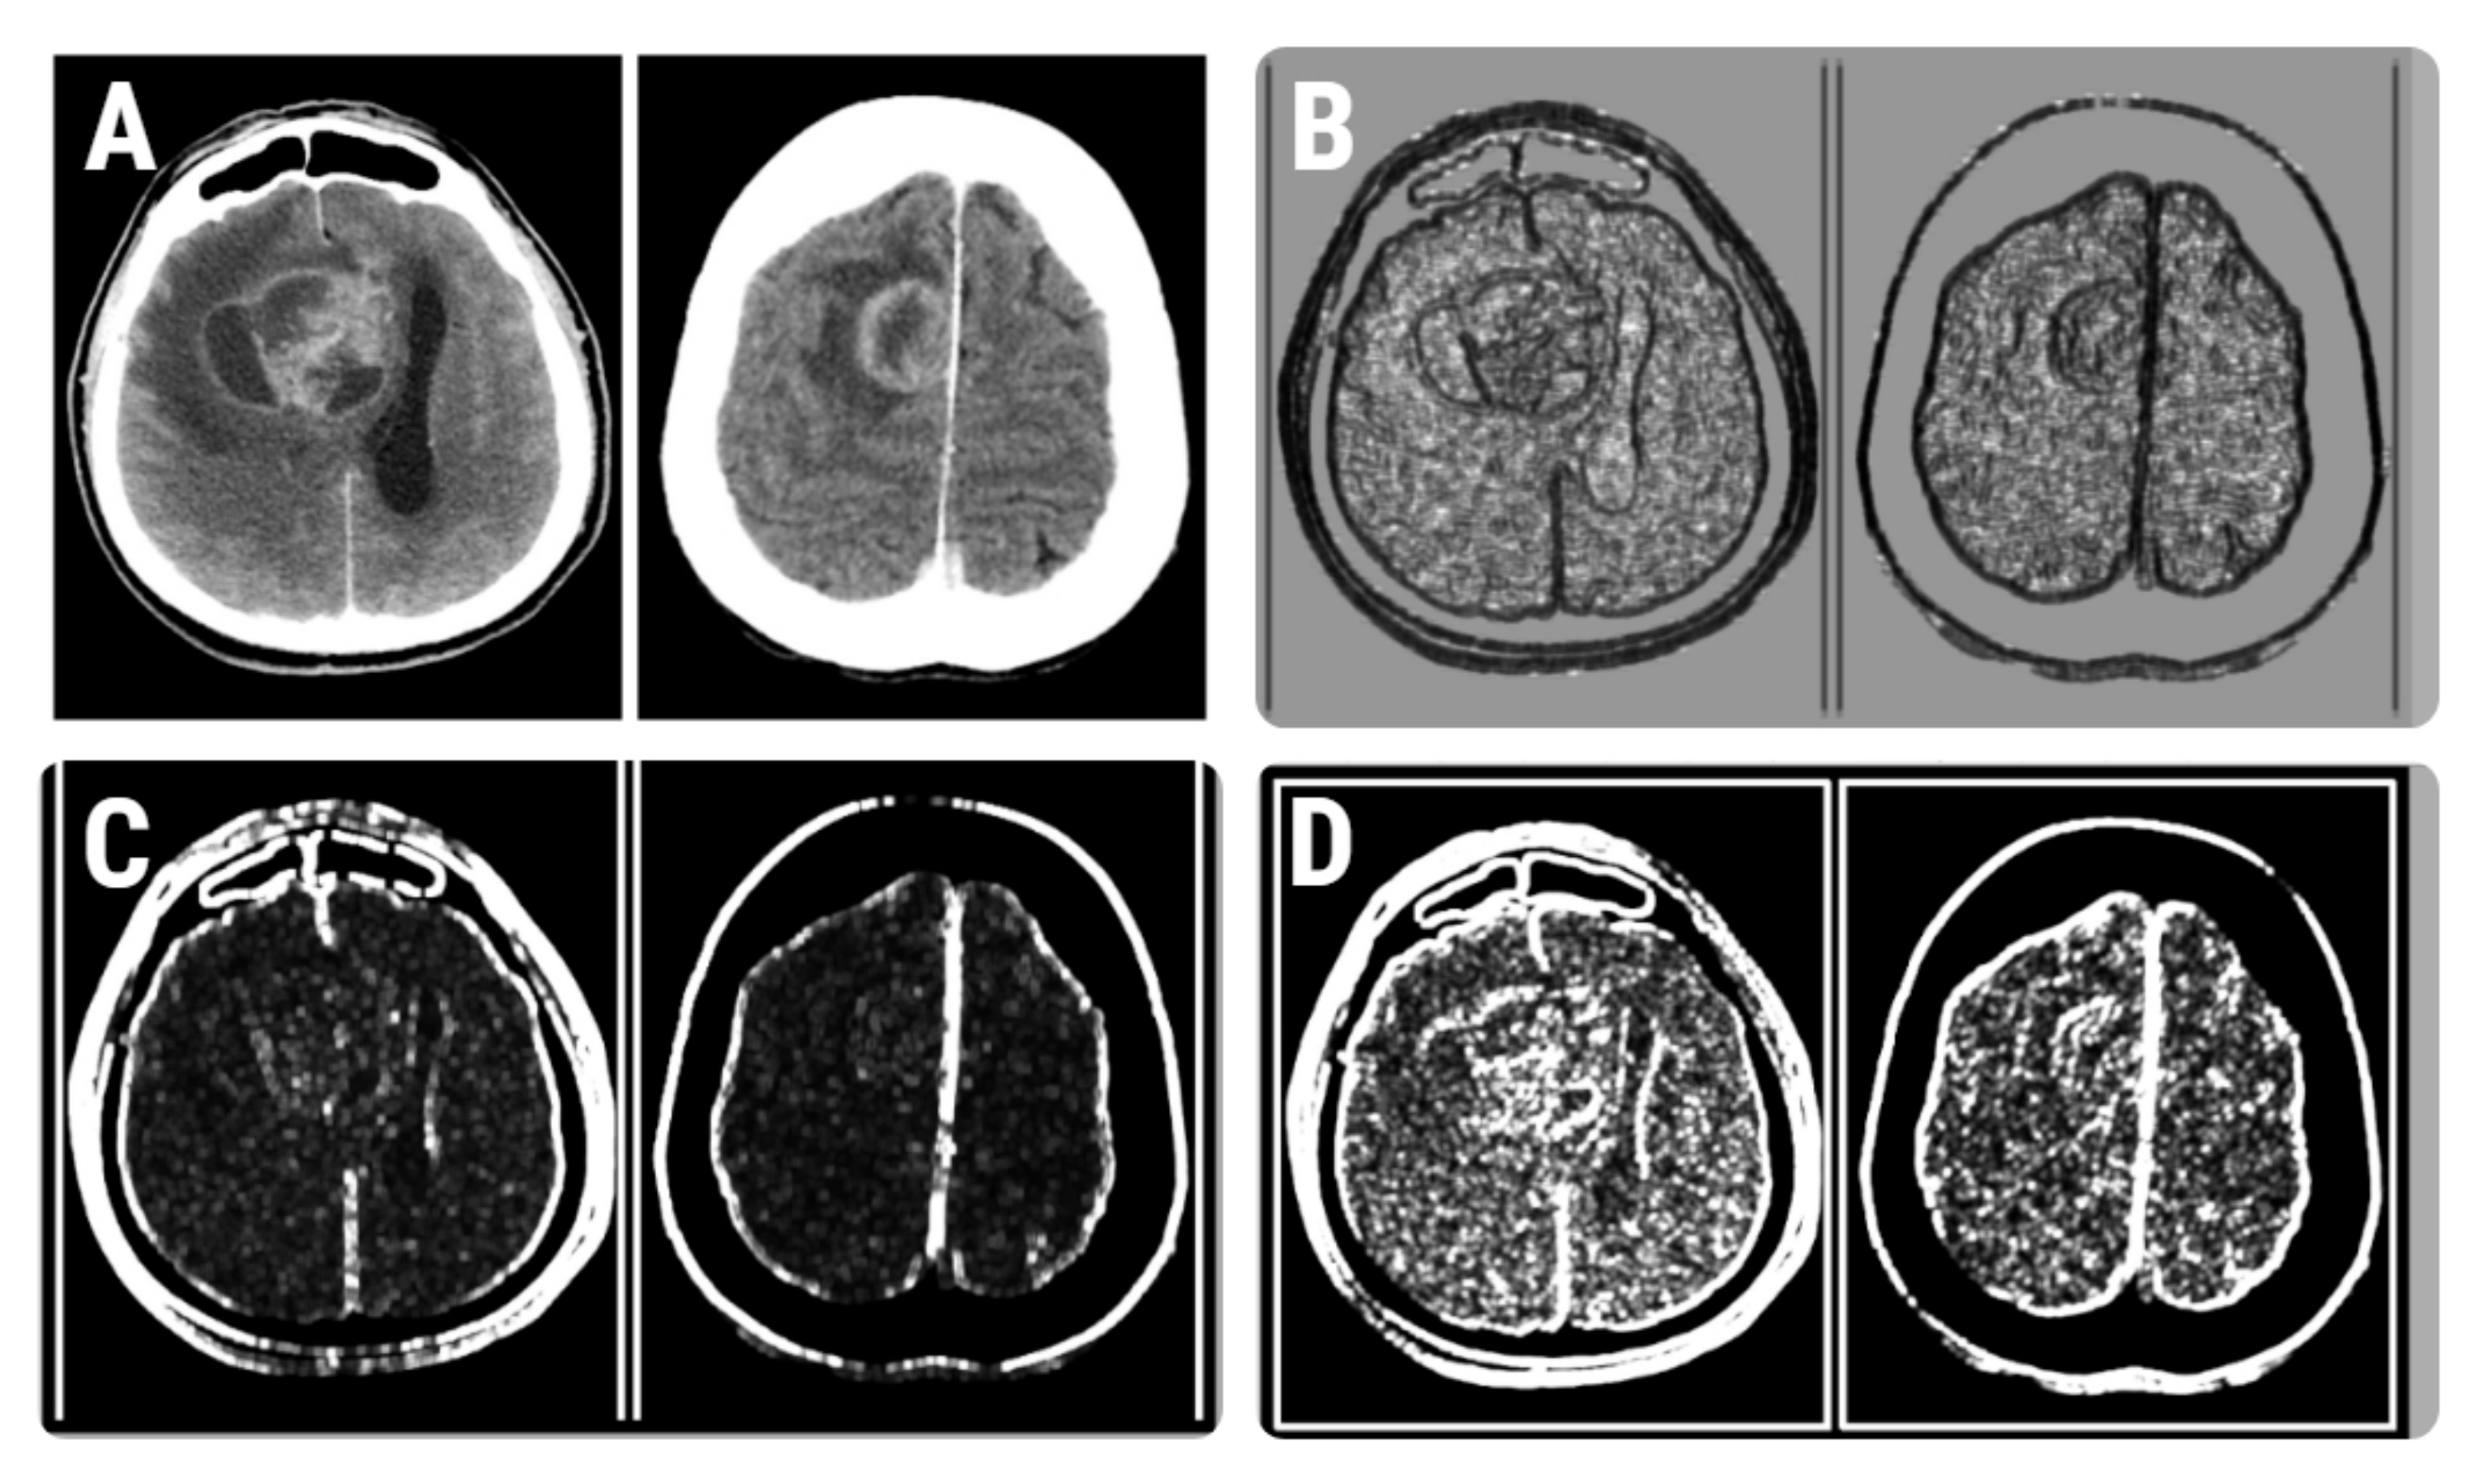

Difference variance is a measure of heterogeneity that places higher weights on differing intensity level pairs that deviate more from the mean [24]. The difference of variance measures the variance of the difference of grey-level values (reflecting the randomness within an image) [25,26]. Both variations of this parameter (CH5D4DifVarnc and CZ2D4DifVarnc) showed higher values for HGGs than for BMs. The parameters’ distribution in CT images of selected cases of HGGs and BMs is shown in Figure 6.

Figure 6.

(A) CT images of patients with histologically proven glioblastoma (left) and brain metastases (right). (B–D) Texture maps that show the distribution of the RZD5GLevNonU (B), CH5D4DifVarnc (C), and contrast (D) parameters in the selected CT images.